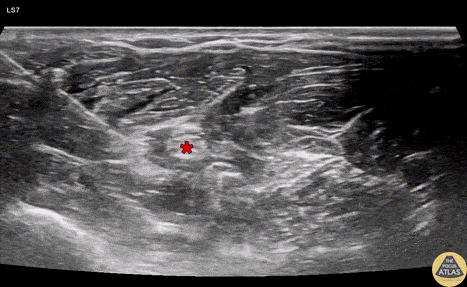

Demonstration of an in-plane radial nerve block, with needle shown entering from the radial aspect, depositing anesthetic deep and radial to the radial nerve (*). Dr. Claudia Quenelle, PGY-3 Denver Health Residency in Emergency Medicine